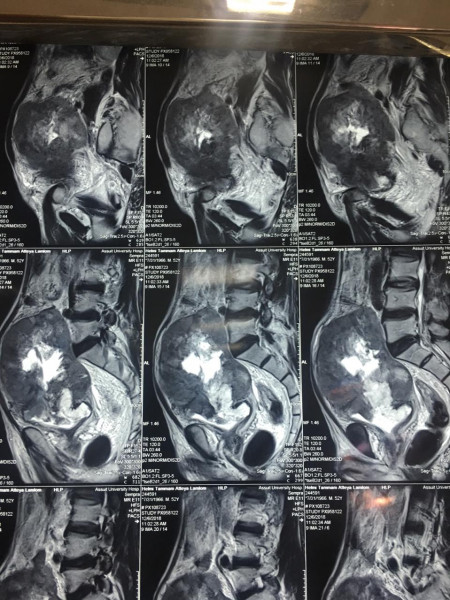

وعن تفاصيل العملية فقد أوضح الدكتور ضياء عبد الحميد الأستاذ بقسم جراحة المسالك البولية والكلى ورئيس وحدة أورام المسالك وقائد الفريق الطبي المسئول عن العملية ، أن تلك العملية تعد من أخطر عمليات استئصال أورام المثانة البولية وذلك نظراً لكبر حجم الورم واختراقه للأمعاء والأنسجة المجاورة من الشرايين والعضلات ، مما يشكل خطورة بالغة على حياه المريض والذي تم تعرضه لظروف معينة تسببت في إهماله للمرض لعدة سنوات، مشيراً أن ذلك تم من خلال التنسيق والتعاون مع أعضاء قسم الجراحة العامة .